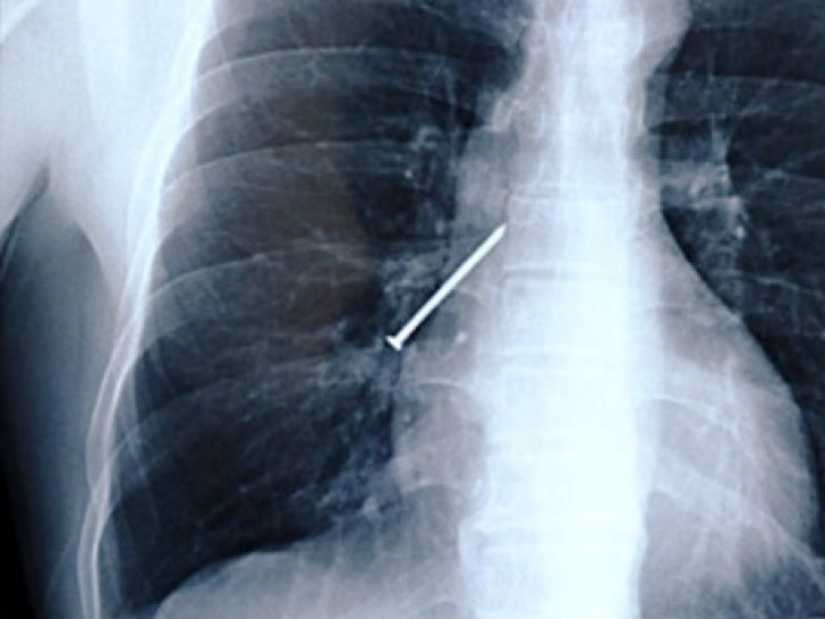

¿Alguna vez has tenido un clavo en los dientes cuando tus manos están ocupadas con un martillo? Aquí hay una foto de un hombre de China que tosió mientras trabajaba.